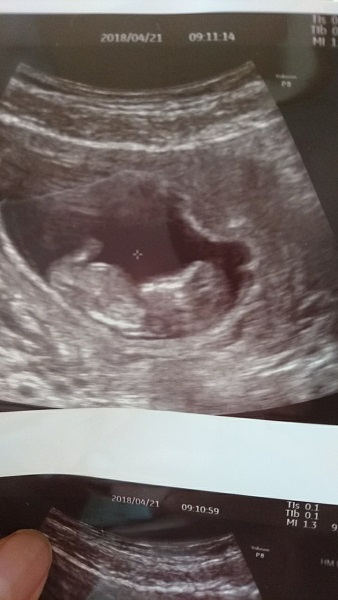

12週1日(12w1d・女の子)|usag1 さん(25歳)

エコー写真撮影時のエピソード:

最初の心拍確認時のエコー。緊急でかかった時だったため、トイレに行っておらず、モヤモヤとしたエコーで、本当に心拍確認できたの?と不安でした。

それから検診の回を重ねるごとにはっきりと人の形になっていくさまが見えて、とてもどきどきで、検診が楽しみだったのを覚えています。